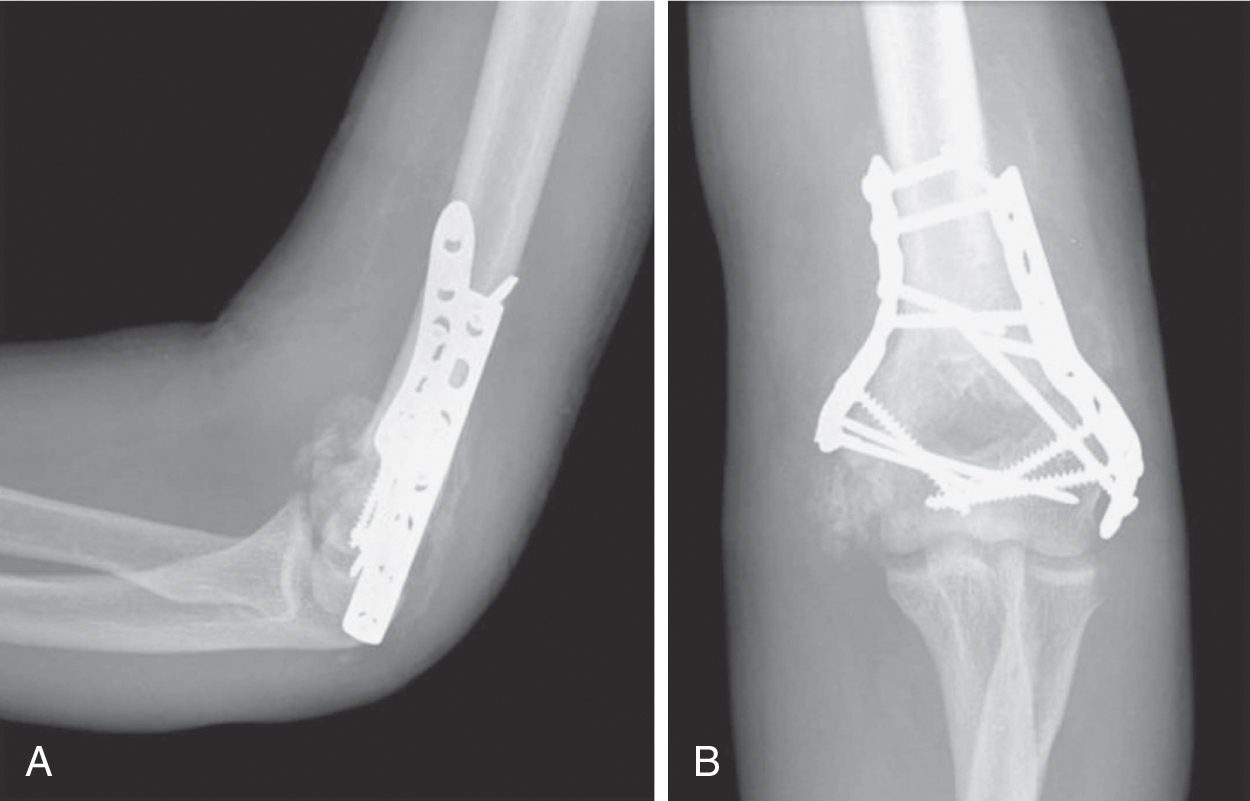

CỐT HÓA LẠC CHỖ (HỘP 43.6)

Cốt hóa lạc chỗ (HO) phổ biến hơn ở những người bị CTSN nặng, bất động, co cứng, gãy xương và rối loạn thần kinh thực vật và có liên quan đến kết quả kém hơn. Các khớp bị ảnh hưởng nhiều nhất là hông và khuỷu tay, tiếp theo là vai, sau đó là gối. Xạ hình xương ba pha có thể xác định HO sớm và không triệu chứng, trong khi chụp X-quang thường quy có thể xác định HO trong các trường hợp nặng hơn. Các dấu ấn máu liên quan đến chuyển hóa xương không đặc hiệu cho HO. Indomethacin, chiếu xạ và etidronate có hiệu quả trong việc ngăn ngừa hình thành HO, nhưng không có bằng chứng nào hỗ trợ điều trị HO cấp tính bằng các tác nhân này.

Hình 43.6 Cốt hóa lạc chỗ Các phim X-quang nghiêng (A) và trước-sau (B) mô tả sự hình thành xương lạc chỗ sau chấn thương sọ não ở khuỷu tay của bệnh nhân sau khi sửa chữa gãy xương.